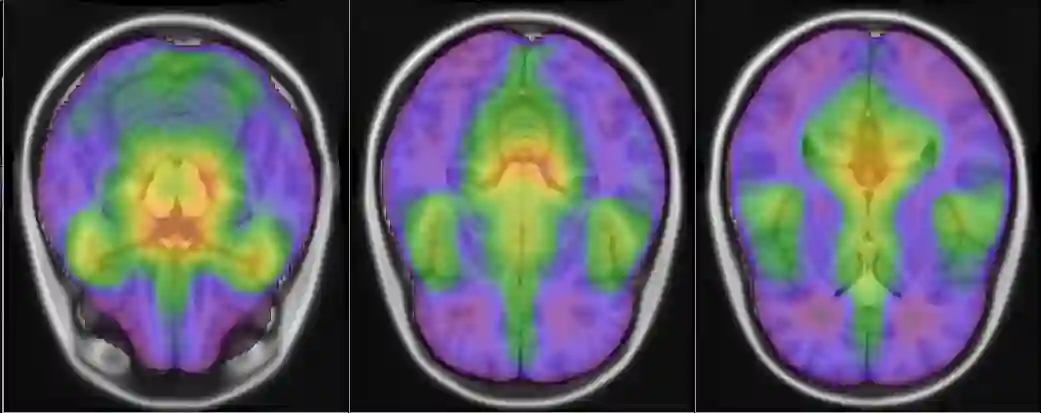

Representational similarity analysis (RSA) is a multivariate technique to investigate cortical representations of objects or constructs. While avoiding ill-posed matrix inversions that plague multivariate approaches in the presence of many outcome variables, it suffers from the confound arising from the non-orthogonality of the design matrix. Here, a partial correlation approach will be explored to adjust for this source of bias by partialling out this confound. A formal analysis will show the dependence of this confound on the temporal correlation model of the sequential observations, motivating a data-driven approach that avoids the problem of misspecification of this model. However, where the autocorrelation locally diverges from the volume average, bias may be difficult to control for exactly (local bias), given the difficulties of estimating the precise form of the confound at each voxel. Application to real data shows the effectiveness of the partial correlation approach, suggesting the impact of local bias to be minor. However, where the control for bias locally fails, possible spurious associations with the similarity matrix of the stimuli may emerge. This limitation may be intrinsic to RSA applied to non-orthogonal designs.